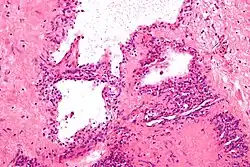

| Micrograph showing a pancreatic serous cystadenoma, a type of cystadenoma. H&E stain. | |